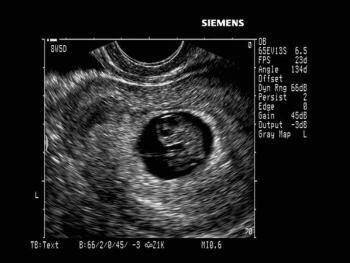

Gynecology Images: Normal Abnormal Obstetric Images: 1st Trimester: Normal Abnormal 2nd Trimester: Normal Abnormal 3rd Trimester: Normal Abnormal Medical Professionals: Upload Your Here Obstetric Images: 3rd Trimester: Normal Normal Thymus - Albana Cerekja Fetal urethra at 31 weeks: just before micturition - Albana Cerekja Normal Female: 4D still image - Effendi Mansoor Monolateral double renal artery,: Normal variant kidney artery supply - Albana Cerekja TRV Fetal Head: BPD and HC Measurements - SIEMENS Velamentosa insertion: 3rd trimester - Effendi Mansoor Umbilical Cord (3D Surface Rendering): Normal Cord - MEDISON SAG Fetal Face, Profile: Fetal Breathing on Color Doppler - SIEMENS 3D Surface Reconstruction: Face - Cayrol Guillermo 3D Surface Reconstruction: Extended Breech Presentation - Saied Mohamed Tohamy 3D Surface Reconstruction: Face - Juan Carlos Pons 3D Surface Reconstruction: Face and Foot - Cayrol Guillermo 3D Surface Reconstruction: Face - Juan Carlos Pons 3D Surface Reconstruction: Face - Juan Carlos Pons